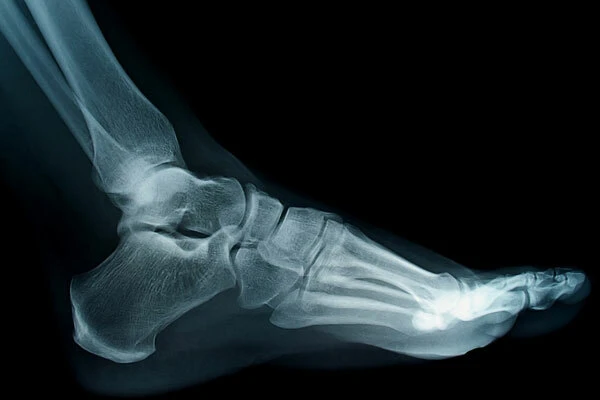

Bàn tay và bàn chân có 106 cái xương, chiếm hơn một nửa số xương trong cơ thể người. Ảnh: Live Science

Xương cũng không phân bố đều trên khắp cơ thể, mà tập trung chủ yếu ở bàn tay và bàn chân. Mỗi bàn tay có 27 cái xương và mỗi bàn chân có 26 cái. Tổng cộng hai bàn tay và hai bàn chân có 106 xương, chiếm hơn một nửa số xương trong cơ người. Riêng xương móng không kết nối với bất kỳ xương nào khác. Đây là một chiếc xương có hình dạng móng ngựa trong cổ họng, nằm giữa cằm và sụn giáp. Xương móng kết hợp với thanh quản và lưỡi để tạo ra tiếng nói của con người.